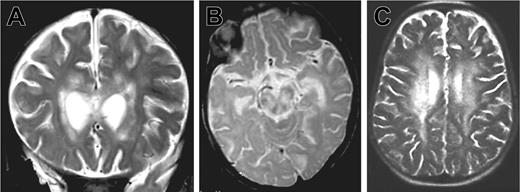

Patient 1 was the third child of consanguineous parents from Algeria. There was no known family history of neurologic disease or early death. Three other siblings were healthy. The patient was hypotrophic at birth (weight 2300 g, length 47 cm, and head circumference 30 cm at 39 weeks gestation). Neurologic symptoms were first noted at 5 months of age after an acute and apparently benign upper respiratory infection: poor head control, tremor of extremities, and abnormal postural tone for age. The patient was hospitalized 2 months later because of the onset of seizures, status epilepticus, ataxia, and coma without fever. Within 2 weeks, the patient developed persistent myoclonus, pyramidal rigidity of lower limbs, right facial weakness, and impaired ocular movements. Two brain magnetic resonance imagings (MRIs) were performed 3 weeks apart at the age of 8 months. Large areas of white matter at periventricular, deep supratentorial, and cerebellar locations were hyperintense in relaxation time (T) 2-weighted and fluid-attenuated inversion recovery (FLAIR) images and hypointense on T1-weighted images and showed contrast enhancement after application of gadolinium (Figure 1A-B). There was also evidence of lesions in the corpus callosum and brain stem mostly in the tegmentum and the pons. No subcortical, cortical, or basal ganglia abnormalities were detected. Lesions were larger on the second MRI. In addition, a moderate degree of hepatosplenomegaly and a 5-cm right cervical mass were detected.

Brain magnetic resonance images of patients 1 and 2. MRIs show large white matter lesions in periventricular areas and brain stem. (A) Patient 1, 7 months, coronal T2 section. (B) Patient 1, 7 months, sagittal T2 section. (C) Patient 2, 33 months, sagittal T2 section.

Patient 2 was the second child of consanguineous parents from the same area of Algeria as family 1. The surnames of patients 1 and 2 were similar and further genetic analyses suggested that both families might be distantly related. Another sibling was healthy. Two maternal uncles died before 3 months of age in Algeria of unknown causes. Two paternal uncles also died in Algeria before the age of 2 years from “meningitis,” although no further information was available. Birth weight and length were unknown. Neurologic symptoms were first retrospectively noted at the age of 6 months: poor head control and abnormal postural tone for age. The patient was admitted to an Algerian hospital for 2 episodes of “aseptic meningitis” at the ages of 7 and 12 months and because of seizures at the age of 24 months. Fever as well as CSF investigations were not documented at that time. He was first admitted to a French hospital 6 months later because of tetraparesis, cognitive impairment (developmental age, 15 months), and seizures. Hepatosplenomegaly was not detected. At that time, routine blood investigations were nearly normal except for hyperlymphocytosis (Table 1). To rule out metabolic diseases, we tested repetitively lactate level, acyl carnitine level, amino acid in plasma, and organic acids in urine and the results were normal. No evidence of low blood sugar was found. Finally, the mitochondrial respiratory chain was studied on mitochondria from lymphocytes, fibroblasts, and liver tissue by polarographic and spectrophometric assays and the results were normal. Brain MRI was performed. Large areas of white matter in the periventricular, deep supratentorial, and cerebellar areas were hyperintense in T2-weighted and FLAIR images and hypointense in T1-weighted images. Contrast enhancement was observed after gadolinium injection. There was also evidence of lesions in the corpus callosum (data not shown).

Three months later (33 months of age), patient 2 was admitted to our hospital with fever, weight loss, and anorexia. Clinical examination revealed massive hepatosplenomegaly. The results of laboratory investigations are shown in Table 1. Severe pancytopenia and a high percentage of HLA DR(+) CD4 and CD8 lymphocytes were observed. In addition, hypertriglyceridemia, hyponatremia, and lymphocytic meningitis were found. Transaminase, fibrinogen, and ferritin levels remained normal. Hemophagocytosis was observed on a bone marrow aspirate. Infection by herpes simplex viruses (HSVA-C), human herpes virus 6 (HHV6), cytomegalovirus (CMV), human immunodeficiency virus (HIV), adenovirus, bacteria, and fungi were excluded. Low copy number of EBV (0.8 log) was detected by PCR in the blood. CSF cultures were negative for bacteria and fungi. A normal level of interferon α (IFN-α; < 2 IU) was detected in the CSF, making viral infection highly unlikely. CSF lactate level was elevated. Treatment consisted of steroids and cyclosporine A (CsA). In 6 days, the hepatosplenomegaly, fever, and biomarkers of disease activity completely regressed, but on the seventh day, an acute neurologic deterioration occurred with coma and choreoathetoid movements. An MRI was performed, showing an extension of the lesions (Figure 1C).